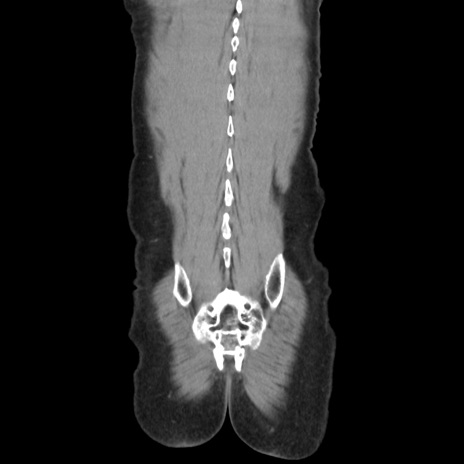

症例37(冠状断像)

【症例】40歳代 男性

【主訴】腹痛

【現病歴】4時間ほど前に電車に乗車中に臍部上より腹痛出現。徐々に増悪し起立困難となり、救急外来受診。生ものは数日食べていない。今朝お雑煮を食べた。

【身体所見】BT 36.8℃、BP 117/84mmHg、HR 91/min、SpO2 97%、苦悶様、腹部:臍上部広範囲圧痛あり、反跳痛±

【データ】WBC 8100、CRP 0.03